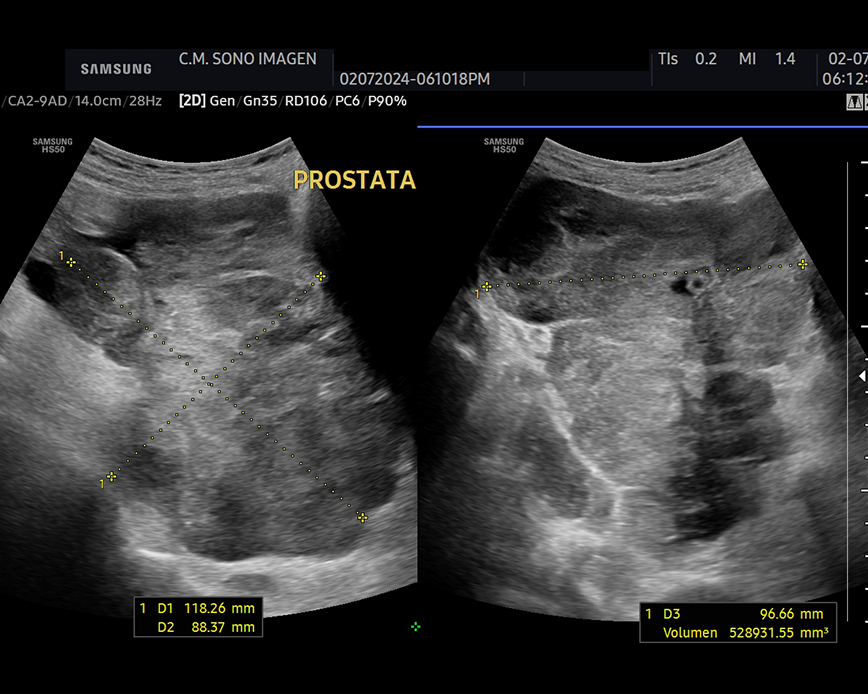

Ecografía Prostática

- hiperplasia prostática benigna(HPB)

- cáncer de próstata

- prostatitis

- dificultad para orinar o retención urinaria